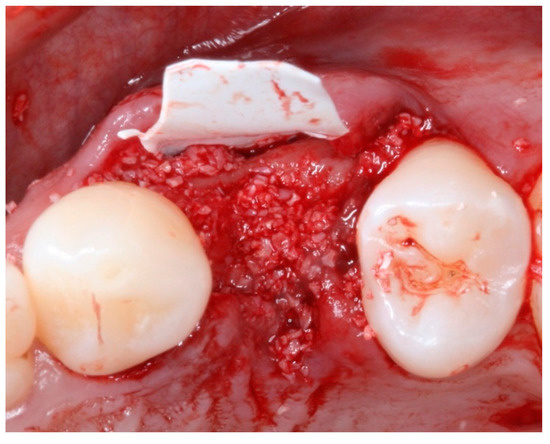

2.4. Groups

2.5. Post-Surgical Procedures